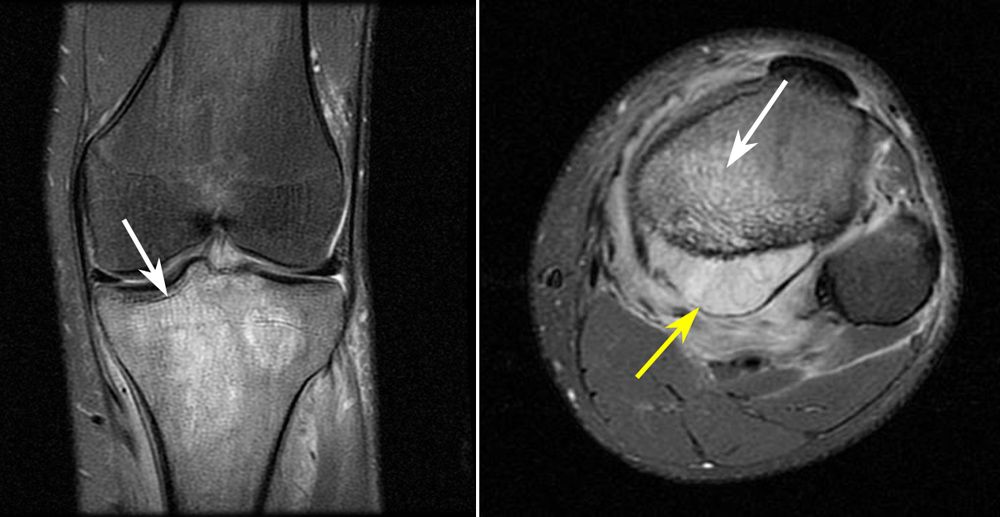

MRI scans of tumor

(Left) This MRI scan shows a tumor at the upper end of the tibia (shinbone). (Right) A cross-sectional MRI of the tumor (white arrow) shows that it has expanded into nearby soft tissues (yellow arrow).

Reproduced from Biermann JS, ed: Orthopaedic Knowledge Update: Musculoskeletal Tumors 3. Rosemont, IL, American Academy of Orthopaedic Surgeons, 2014, p 206.